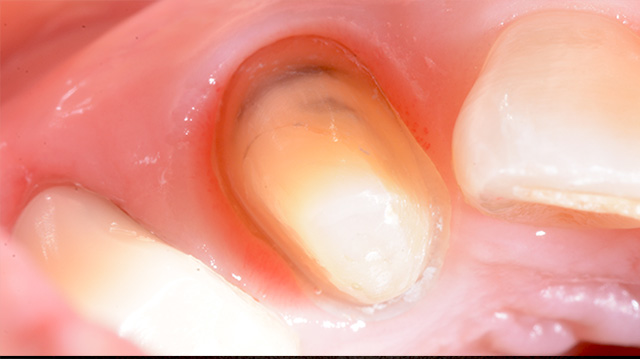

| 年代・性別 | 40代 男性 |

|---|---|

| 主訴 | 前歯の被せ物が取れた |

| 治療回数 | 3回 |

| 治療期間 | 約1ヶ月 |

| 費用 | 仮歯 5,500円 ジルコニアクラウン 176,000円 |